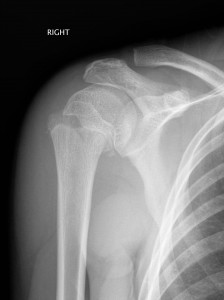

Above: Salter-Harris II fracture of proximal humerus

Proximal Humerus Fractures

- Younger children are prone to buckle fractures of the proximal humerus.

- Adolescents are more likely to have Salter-Harris fractures around the physis.

- The degree of angulation is usually not an issue. This will correct with gravity and remodelling.